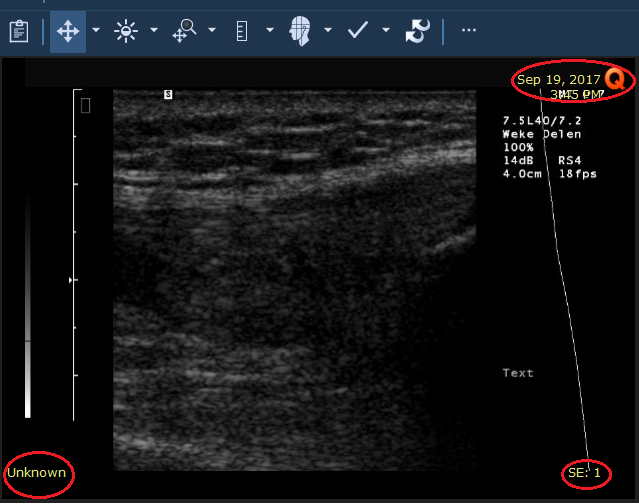

Εξέταση ασθενούς όπου αποκρύπτονται οι δημογραφικές πληροφορίες ![]() | Εξέταση ασθενούς όπου εμφανίζονται οι δημογραφικές πληροφορίες (σε κύκλο) ![]() |